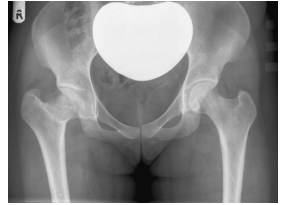

Observe a figura abaixo.

As setas indicam

Provas